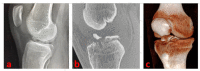

Materials and methods: Standard and patient-specific accessory arthroscopic portals allow for full access to knee visualization and management of concomitant intraarticular lesions. After performing the debridement of the inflammatory tissue and the release of eventual interposed tissues in the fracture site, the tibial eminence avulsion can be reduced by using a less-invasive bone impactor. With the knee flexed to 90°, the fracture fragments are then synthesized (under fluoroscopic control) with three thin Kirschner wires inserted in a proximal-distal direction in a cross-shaped geometry.